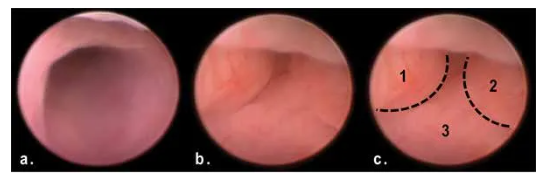

2. AOM/DSS造模50天后,与正常结肠(a)相比,模型组产生了多发性息肉样肿块阻塞末端结肠管腔(b、c)。